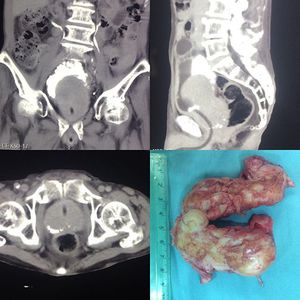

82 y.o male with urinary obstruction symptoms for more than 15 years. Huge prostate palpate through rectal examination. On CT reveal a indentation of protate to vesicae. Open prostatectomy (Frayer technique) was choosen as management